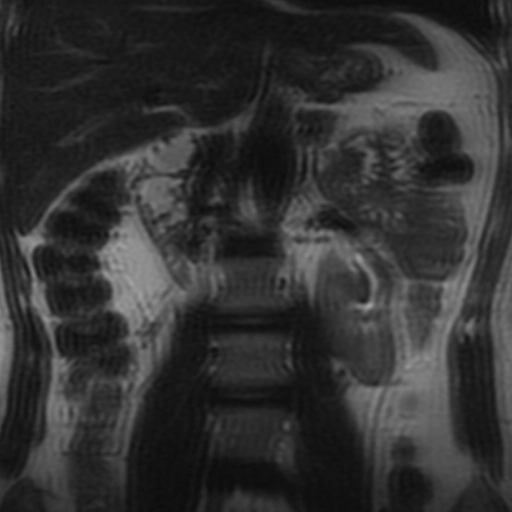

Tắc nghẽn chỗ nối bể thận-niệu quản (Ureteropelvic junction obstruction - UPJ obstruction)